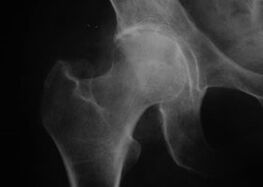

Coxaarthrosis, arthrosis of the hip joint

With this disease, a classic clinical picture of arthrosis is observed.

The first symptom of coxarthrosis is discomfort in the hip joint after physical activity.

With progressive coxarthrosis, pain increases, stiffness and limited mobility appear.

Patients with a severe form of coxarthrosis spare the affected limb, avoiding stepping on it and being immobile, choose positions in which the pain is felt less.